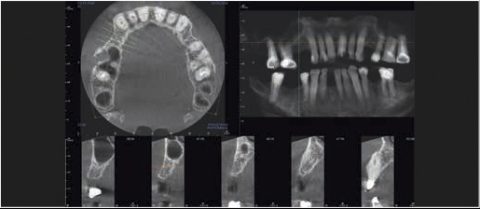

Tomografia komputerowa jest niezastąpiona w planowaniu leczenia implantologicznego i chirurgicznego. W wielu przypadkach pozwala uniknąć powikłań podczas leczenia kanałowego jeszcze przed jego rozpoczęciem. Wysokiej rozdzielczości badanie mikroCBCT (endoCBCT) precyzyjnie obrazuje architekturę systemu kanałowego zęba. Na jego podstawie lekarz może ocenić ilość kanałów, ich krzywiznę oraz ewentualne połączenia.

Cztery różne pola obrazowania zapewniają niezawodną diagnostykę 3D w całym obszarze jamy ustnej. Zapewniają one precyzyjne dopasowanie, odpowiednie do wskazań a także uniwersalne możliwości zastosowania w codziennej praktyce – od endodoncji, poprzez implantologię do chirurgii jamy ustnej.